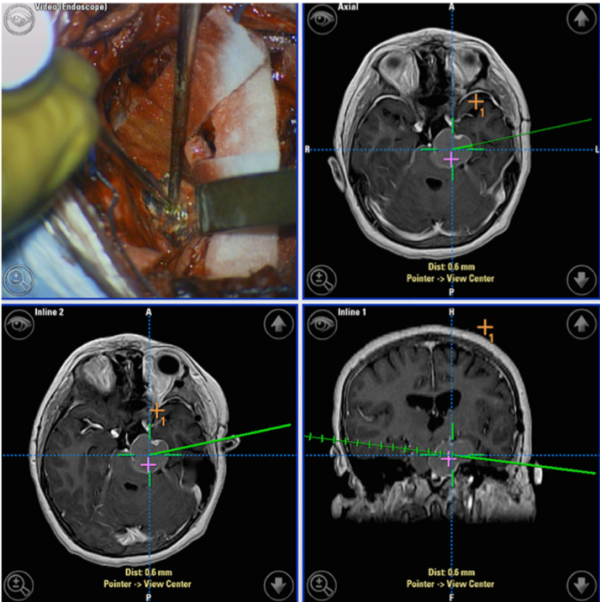

圖:復(fù)雜的囊性顱咽管瘤的術(shù)中導(dǎo)航屏幕截圖,顯示左中腦凹陷并延伸到左小腦橋角,神經(jīng)導(dǎo)航可有助于擴(kuò)展性復(fù)雜病變的手術(shù)切除。